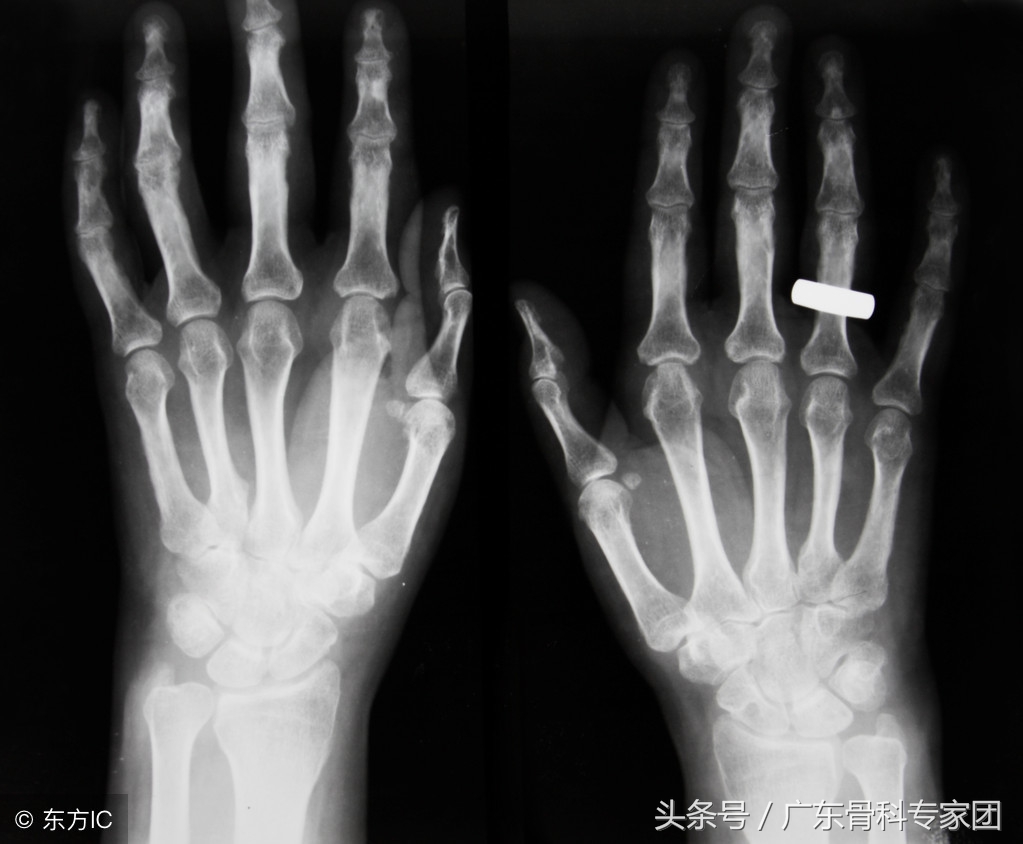

骨质疏松是由于多种原因引起的一组骨病,骨组织有正常的钙化,钙盐和基质呈不正常的比例,并且单位体积内骨组织量在减少。

导致骨质疏松的原因主要分为两方面,原发性和继发性。骨质疏松最重要的表现为疼痛,这是最常见的症状,而且很多患者的疼痛部位出现在腰背部。很多患者在疼痛之后会出现身长缩短,驼背的现象。而且很多老年人随着年纪的增长,骨质疏松加重,驼背的曲度会加大。对于骨质疏松患者来说,出现的最严重的并发症可以说就是骨折了,有时候还伴有呼吸功能下降。